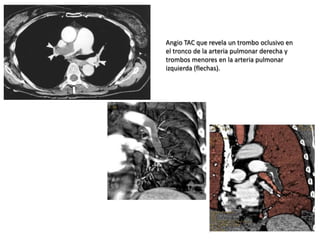

TAC Helicoidal Es latécnica de elección. Permite la visualización directa del trombo dentro de la arteria pulmonar y sus ramas.

Angio TAC querevela un trombo oclusivo en el tronco de la arteria pulmonar derecha y trombos menores en la arteria pulmonar izquierda (flechas).